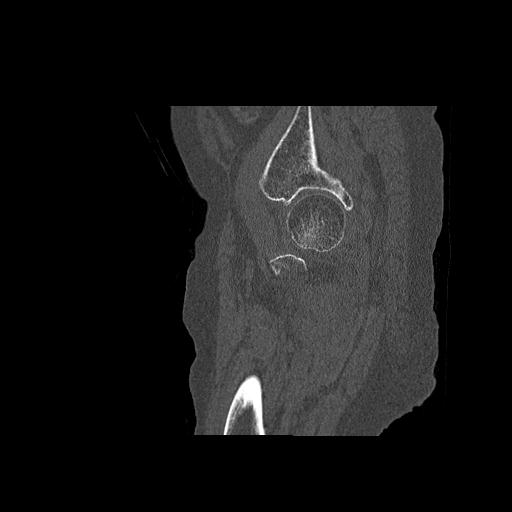

102755 1/4 2R 1/15 2R 右足関節 68歳女性 右三果脱臼骨折